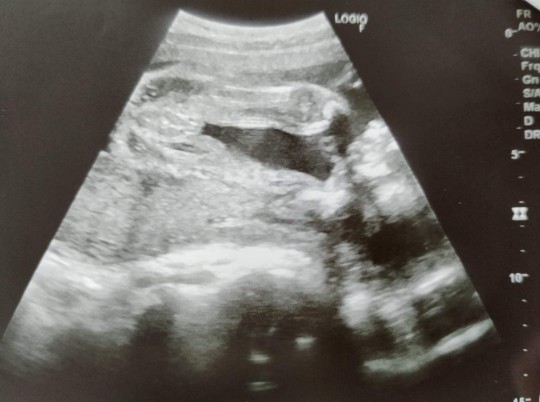

ฝากดูด้วยค่ะว่านี้ญ.หรือช.

น่าจะผช.นะคะ ไข่กลมเชียว😁😁😁

VIP Member

ชายค่ะ ทั้งพวงทั้งจู๋ ชัดมาก

ผู้ชายค่ะ เห็นทั้งพวงเรย 😂😂

โอ๊ยยยแม่ไข่มาเป็นพวงเลยยย

ไข่มาเป็นพวงเลยค่ะแม่ 😁😁😁